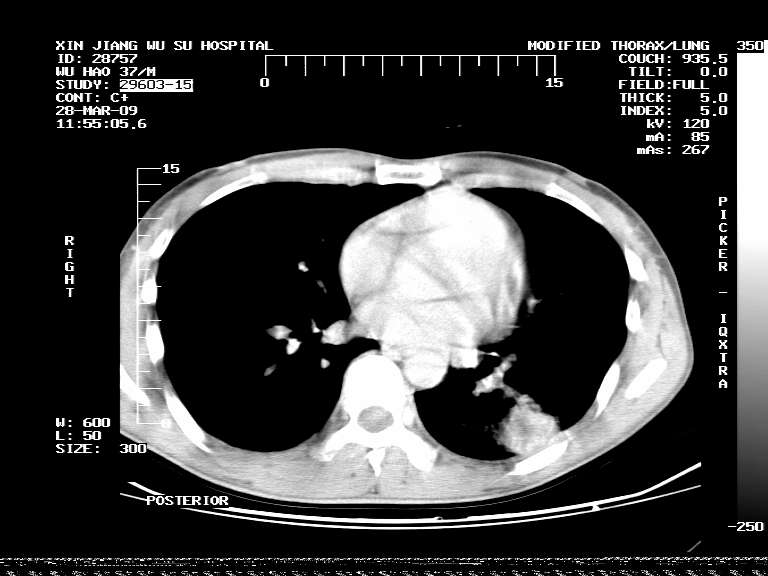

男,37岁,体检胸透发现阴影。

患者体检发现 无症状 左肺下叶占位,边缘模糊,可见血管聚束、分叶、胸膜牵拉,增强呈不均匀性强化。 首先考虑左肺下叶周围型肺癌,建议穿刺活检。

患者体检发现 无症状 左肺下叶占位,边缘模糊,可见血管聚束、分叶、胸膜牵拉,增强呈不均匀性强化。 首先考虑左肺下叶周围型肺癌,建议穿刺活检。支持!

左肺下叶见一结节病变,边缘欠清不光滑,与胸膜粘连且胸膜局限性增厚,注药后呈环形强化,动脉期壁呈明显点环状强化,静脉期壁强化减低,中心密度低无强化,灶周无明显的卫星灶和水肿区(晕征)---考虑周围性肺癌,不除外感染性病变,建议穿刺活检。

左肺下叶软组织病灶,密度较高,内见点状钙化,其周围见子灶,邻近胸膜扁平样增厚.c+病灶强化明显,中心强化弱.诊断:左肺下叶结核瘤.

左肺下叶大片实变影,内靠胸膜见不规则更高密度结节灶,边缘强化,相邻胸膜增厚,胸膜下脂肪线存在。考虑炎症,结核可能。